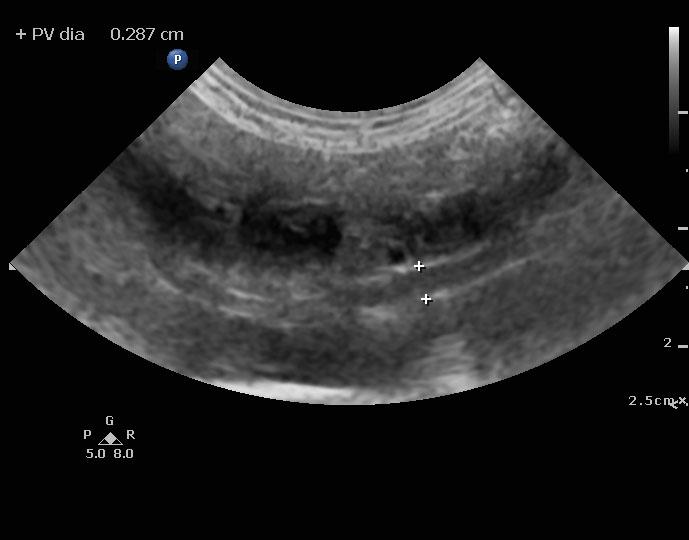

An 8-year-old spayed female Maltese dog was presented for evaluation of severely elevated pre-and post-prandial bile acids. In addition, the patient was positive for Rocky Mountain spotted fever. Seizure activity was present in the history